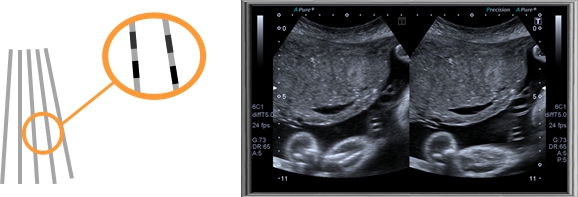

DDD二維、彩色雙幅動態(tài)實時顯示技術(shù)

二維、彩色雙福動態(tài)實時顯示技術(shù)允許系統(tǒng)同步顯示二維圖像和彩色多普勒圖像,便于同時觀察組織結(jié)構(gòu)和血流動力學(xué)變化。使原來只能在兩個顯示器上實現(xiàn)的功能在同一顯示器上就能實現(xiàn),使感興趣區(qū)不會在頻繁的轉(zhuǎn)換模式時丟失,而且為臨床介入治療準確穿刺定位提供了實時監(jiān)測手段,避免周圍血管損傷。